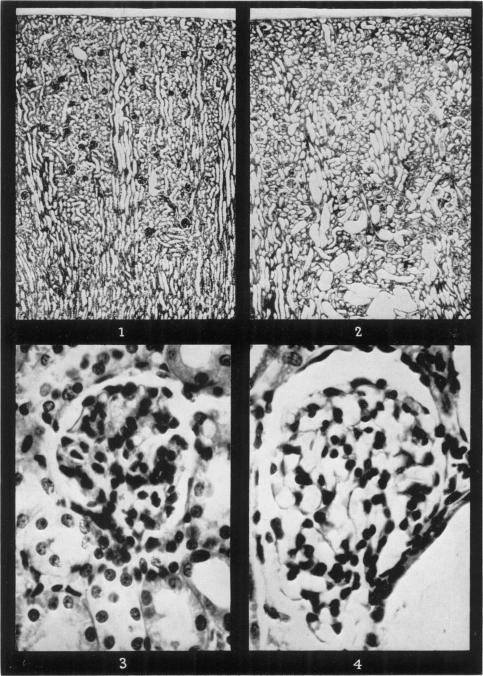

Cortisone-induced renal changes in the rabbit: a microdissection study.

Br J Exp Pathol. 1960 Apr;41(2):140-9.